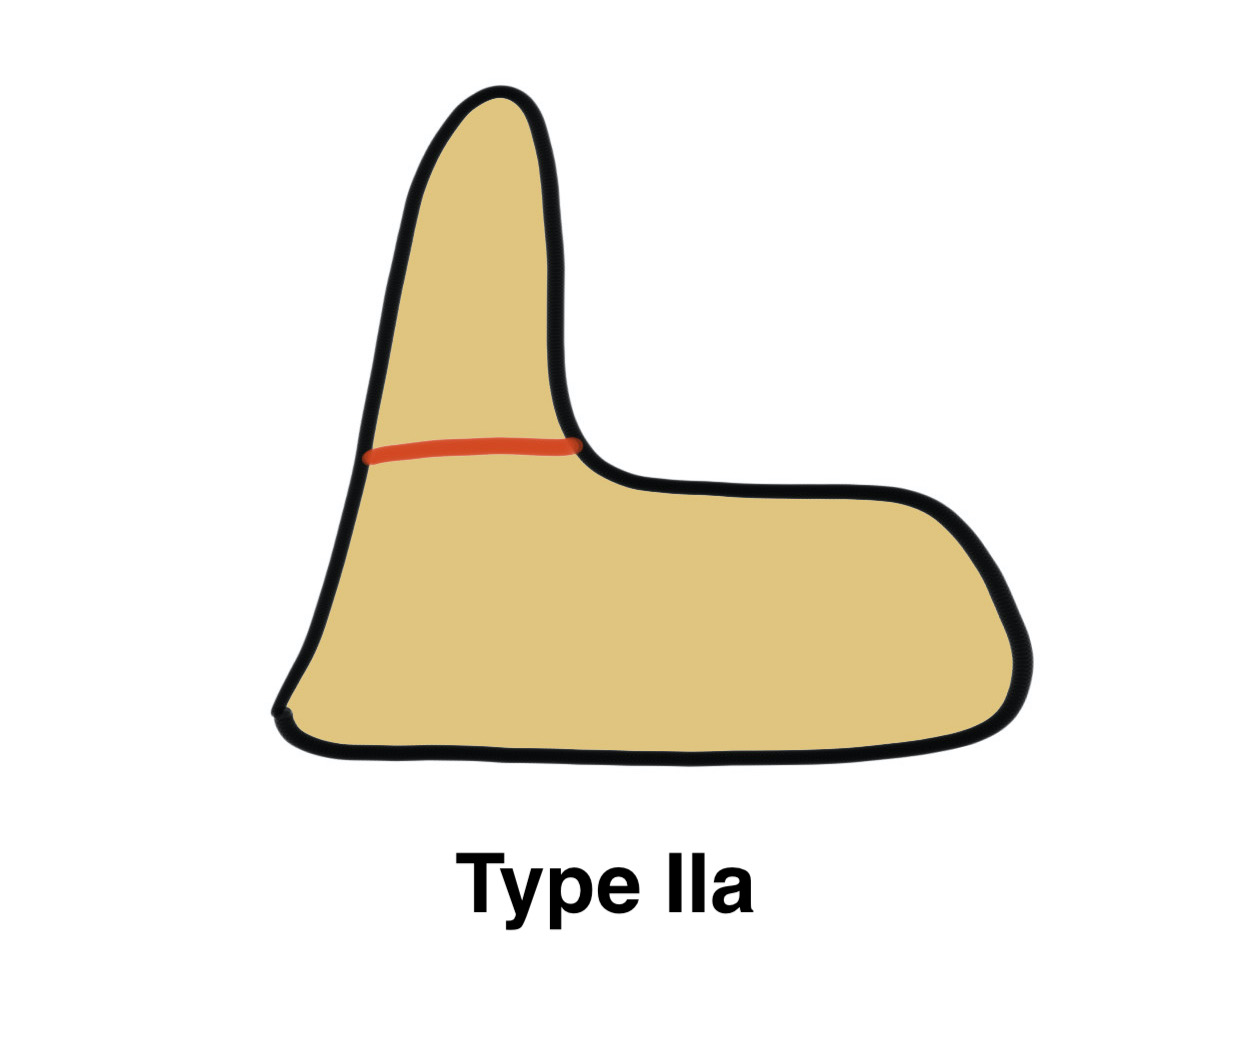

Grauer classification of Type II

| Type | Definition | Management |

| Type IIa |

Non or mimimally displaced No comminution |

Non operative treatment |